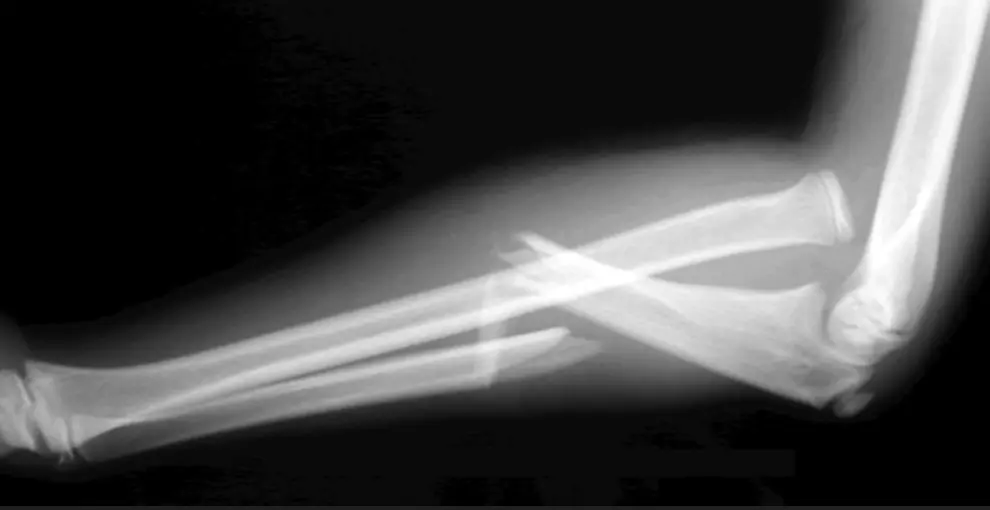

- Anatomical reduction is a must to preserve function

- 2 fractures at the same level = 100% unstable